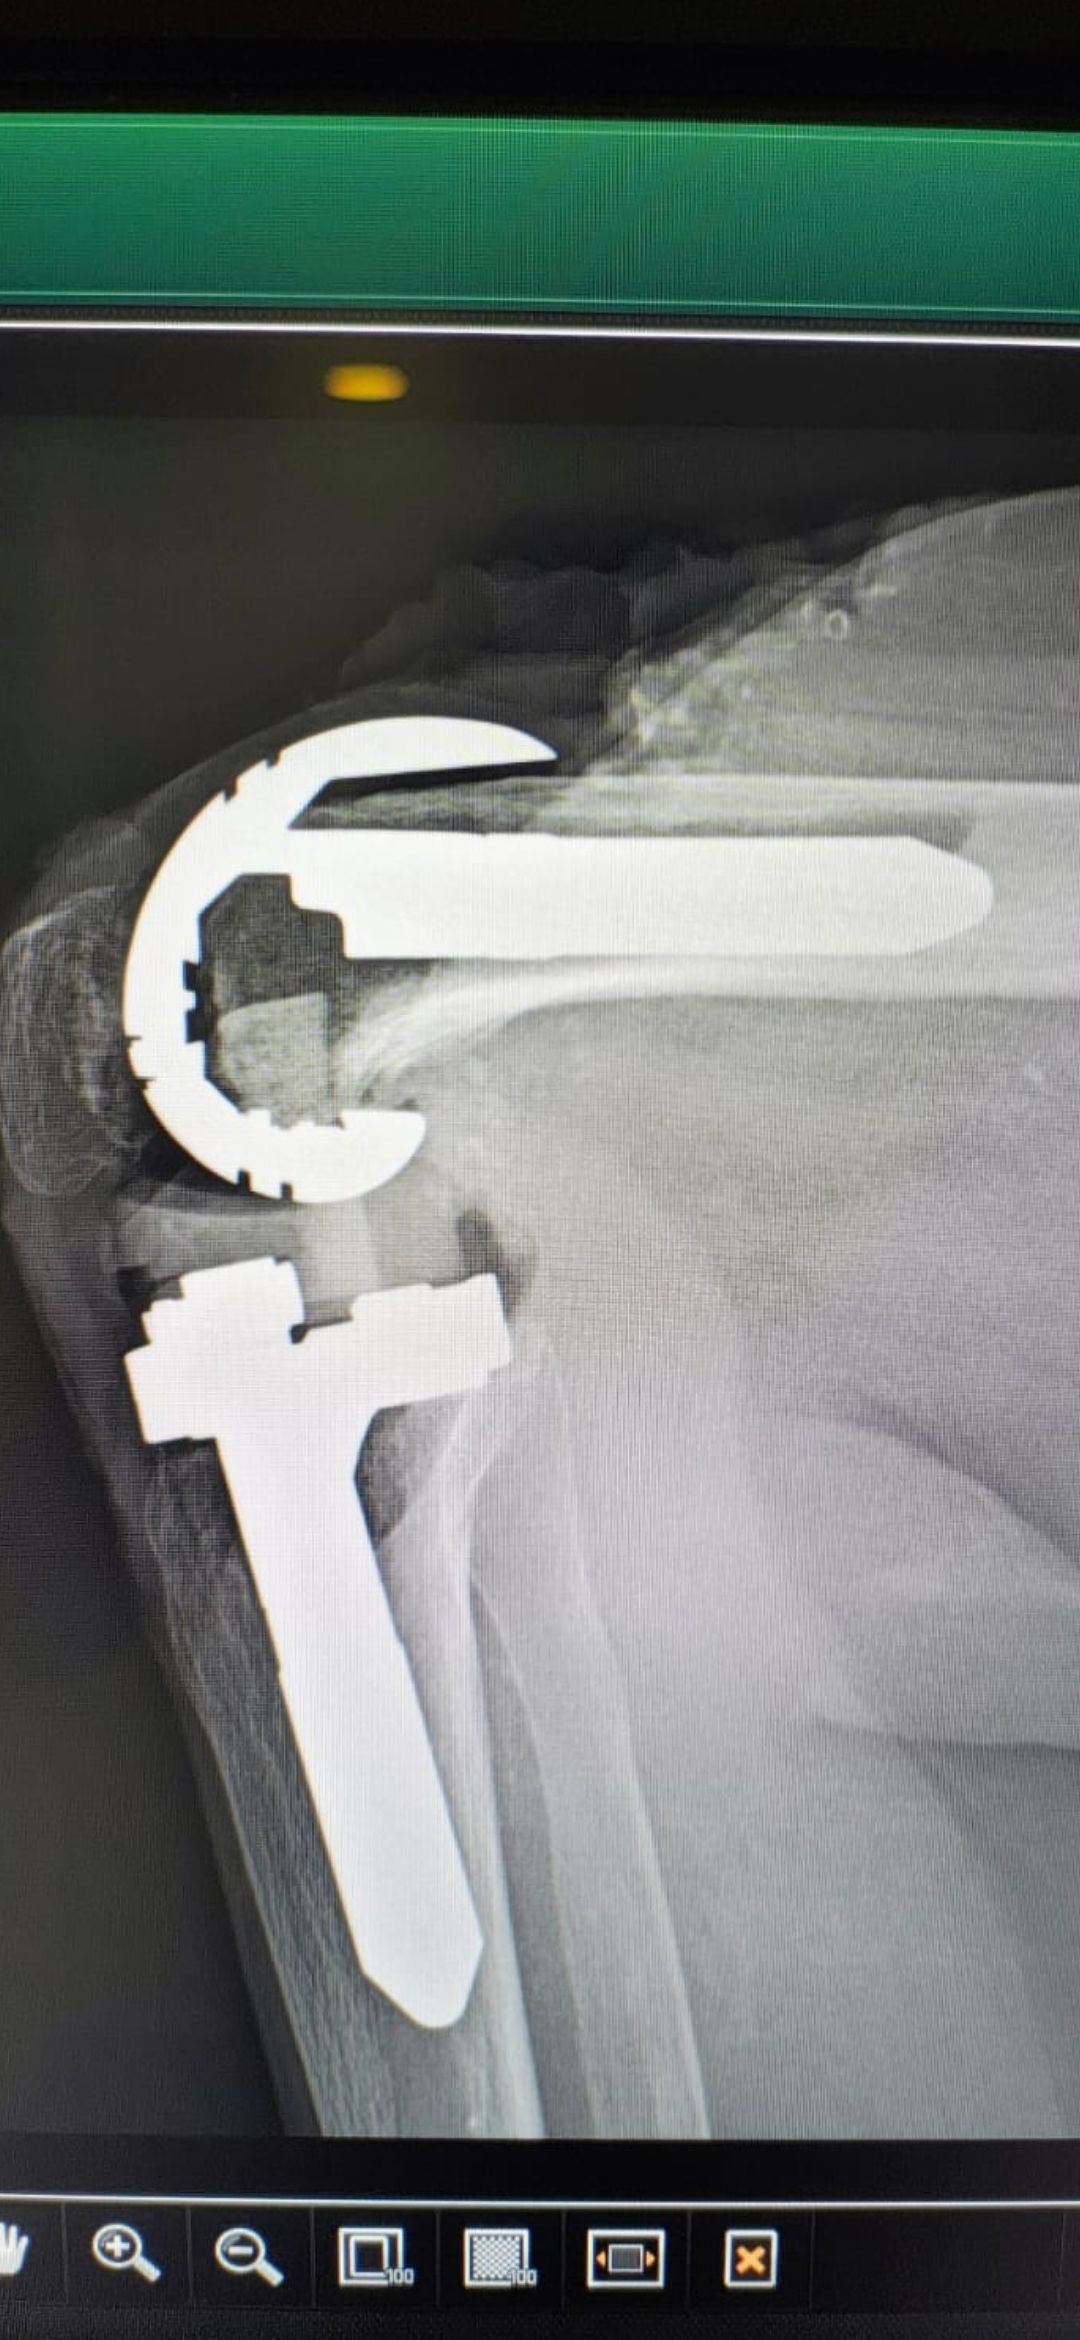

Soy   egresado  de  la  Universidad Autonoma de   Nuevo  Leon. especialidad de ortopedia y traumatologia  en    hospital  numero  21  del  IMSS ne Monterrey  N.L ,con entrenamiento en la  subespecialidad  de   reconstrucion  articular  y  artroscopia  que incluye  lesiones  de  meniscos  , reconstruccion de ligamentos cruzados , lesiones  condrales ,  gonartrosis   tengo  una  historia laboral    institucional de 30  años    hasta el 30  de lulio del 2024 estuve  10  años  en  el  modulo  de  artroscopia  con aproximadamente   1120    artroscopias  de rodilla   y  15 años  en  el  departamento  de    artroplastia  de rodilla  o  de  reemplazos  articulares   ,  los  ultimos   15  años    como profesor  adjunto   y titular  en los cursos    de pre  y posgrados  de  traumatologos  en la  subespecialidad  de  con aproximadamente   160 cirugias  institucionales    en   artroplastia de  rodilla    por  cada año   y  un  numero menor en el  medio particular  dando un total  aproximado  de  2,560  cirugias . de  estas  el  10%    de  revision  y  5%  preotesis    tumorales    de  actualmente   en  funciones  en  el  medio privado  y  acreditado  en todos los  hospitales  de la  localidad  y  con todas  las  aseguradoras   de  gastos  medicos .